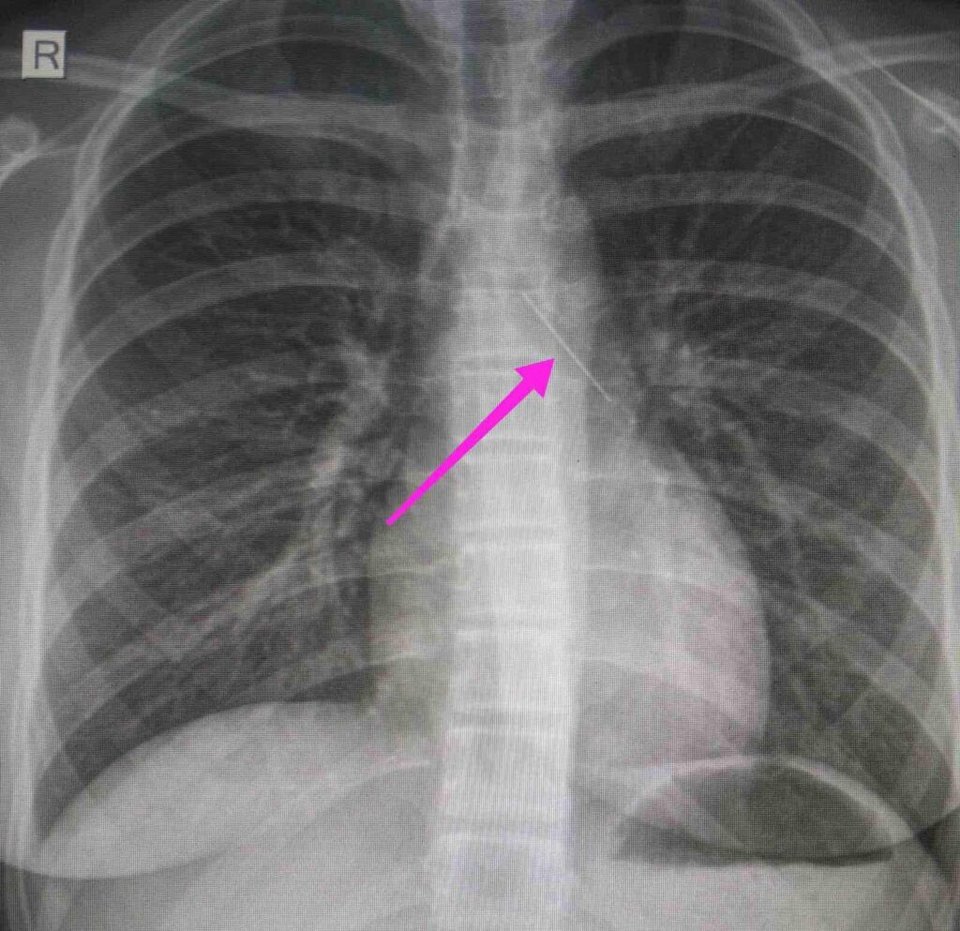

Από την ακτινογραφία θώρακος και την αξονική τομογραφία θώρακος διαπιστώθηκε «η ύπαρξη αιχμηρού μεταλλικού ξένου σώματος στην αναπνευστική οδό (αριστερός κύριος βρόγχος) και όχι στην πεπτική οδό» αναφέρει, μεταξύ άλλων, η ανακοίνωση του νοσοκομείου.

«Χθες 30/1/2022 στις 16:00 στο Τ.Ε.Π. του ΓΝΘ Ιπποκράτειο, προσήλθε ανήλικη συνοδευόμενη από τους γονείς της, μετά από αναφερόμενη κατάποση ξένου σώματος (καρφίτσα). Από την απεικονιστική διερεύνηση που πραγματοποιήθηκε με ακτινογραφία θώρακος αρχικά και ακολούθως με αξονική τομογραφία θώρακος, διαπιστώθηκε η ύπαρξη αιχμηρού μεταλλικού ξένου σώματος στην αναπνευστική οδό (αριστερός κύριος βρόγχος) και όχι στην πεπτική οδό.

Κατά την βρογχοσκόπηση διαπιστώθηκε η μετακίνηση και ενσφήνωση του ξένου σώματος στον δεξιό κύριο βρόγχο. Μετά οπό εργώδεις προσπάθειες ολοκληρώθηκε με επιτυχία η αφαίρεση αυτού. Η ασθενής ανένηψε πλήρως εντός της χειρουργικής αίθουσας. Η ασθενής μεταφέρθηκε για παρακολούθηση και νοσηλεία στη Γ’ Παιδιατρική Κλινική.